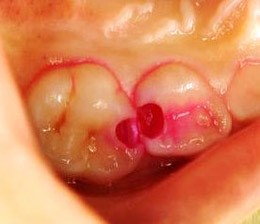

神経が露出しているなら「直接覆髄法」

虫歯が深くなっている症例では、虫歯を削ると神経が露出してしまうことがあります。歯の神経は細菌感染しやすく、感染すると炎症を引き起こします。こうした症例の治療では、細菌の感染と炎症を防ぐことを考慮しなければなりません。

このような場合に露出した神経を保護する治療方法が、「直接覆髄法」です。上でご紹介した「MTAセメント」で神経を直接覆うことで、殺菌・保護します。

「断髄法」で炎症部分のみを除去

虫歯が深く進行し神経に到達すると神経を取る治療を提案されます。しかし、炎症が神経の一部に限られている場合は、全ての神経を除去する必要はなく、部分的な治療が可能です。このような状況で利用されるのが「部分断髄法」という治療法です。

この治療では、炎症を起こしている神経の部分だけを慎重に切除し、残りの健康な神経を保存します。切除した部分はMTAセメントやバイオセラミックで保護し、覆うことによって、神経のさらなる損傷を防ぎつつ、歯の機能を維持します。